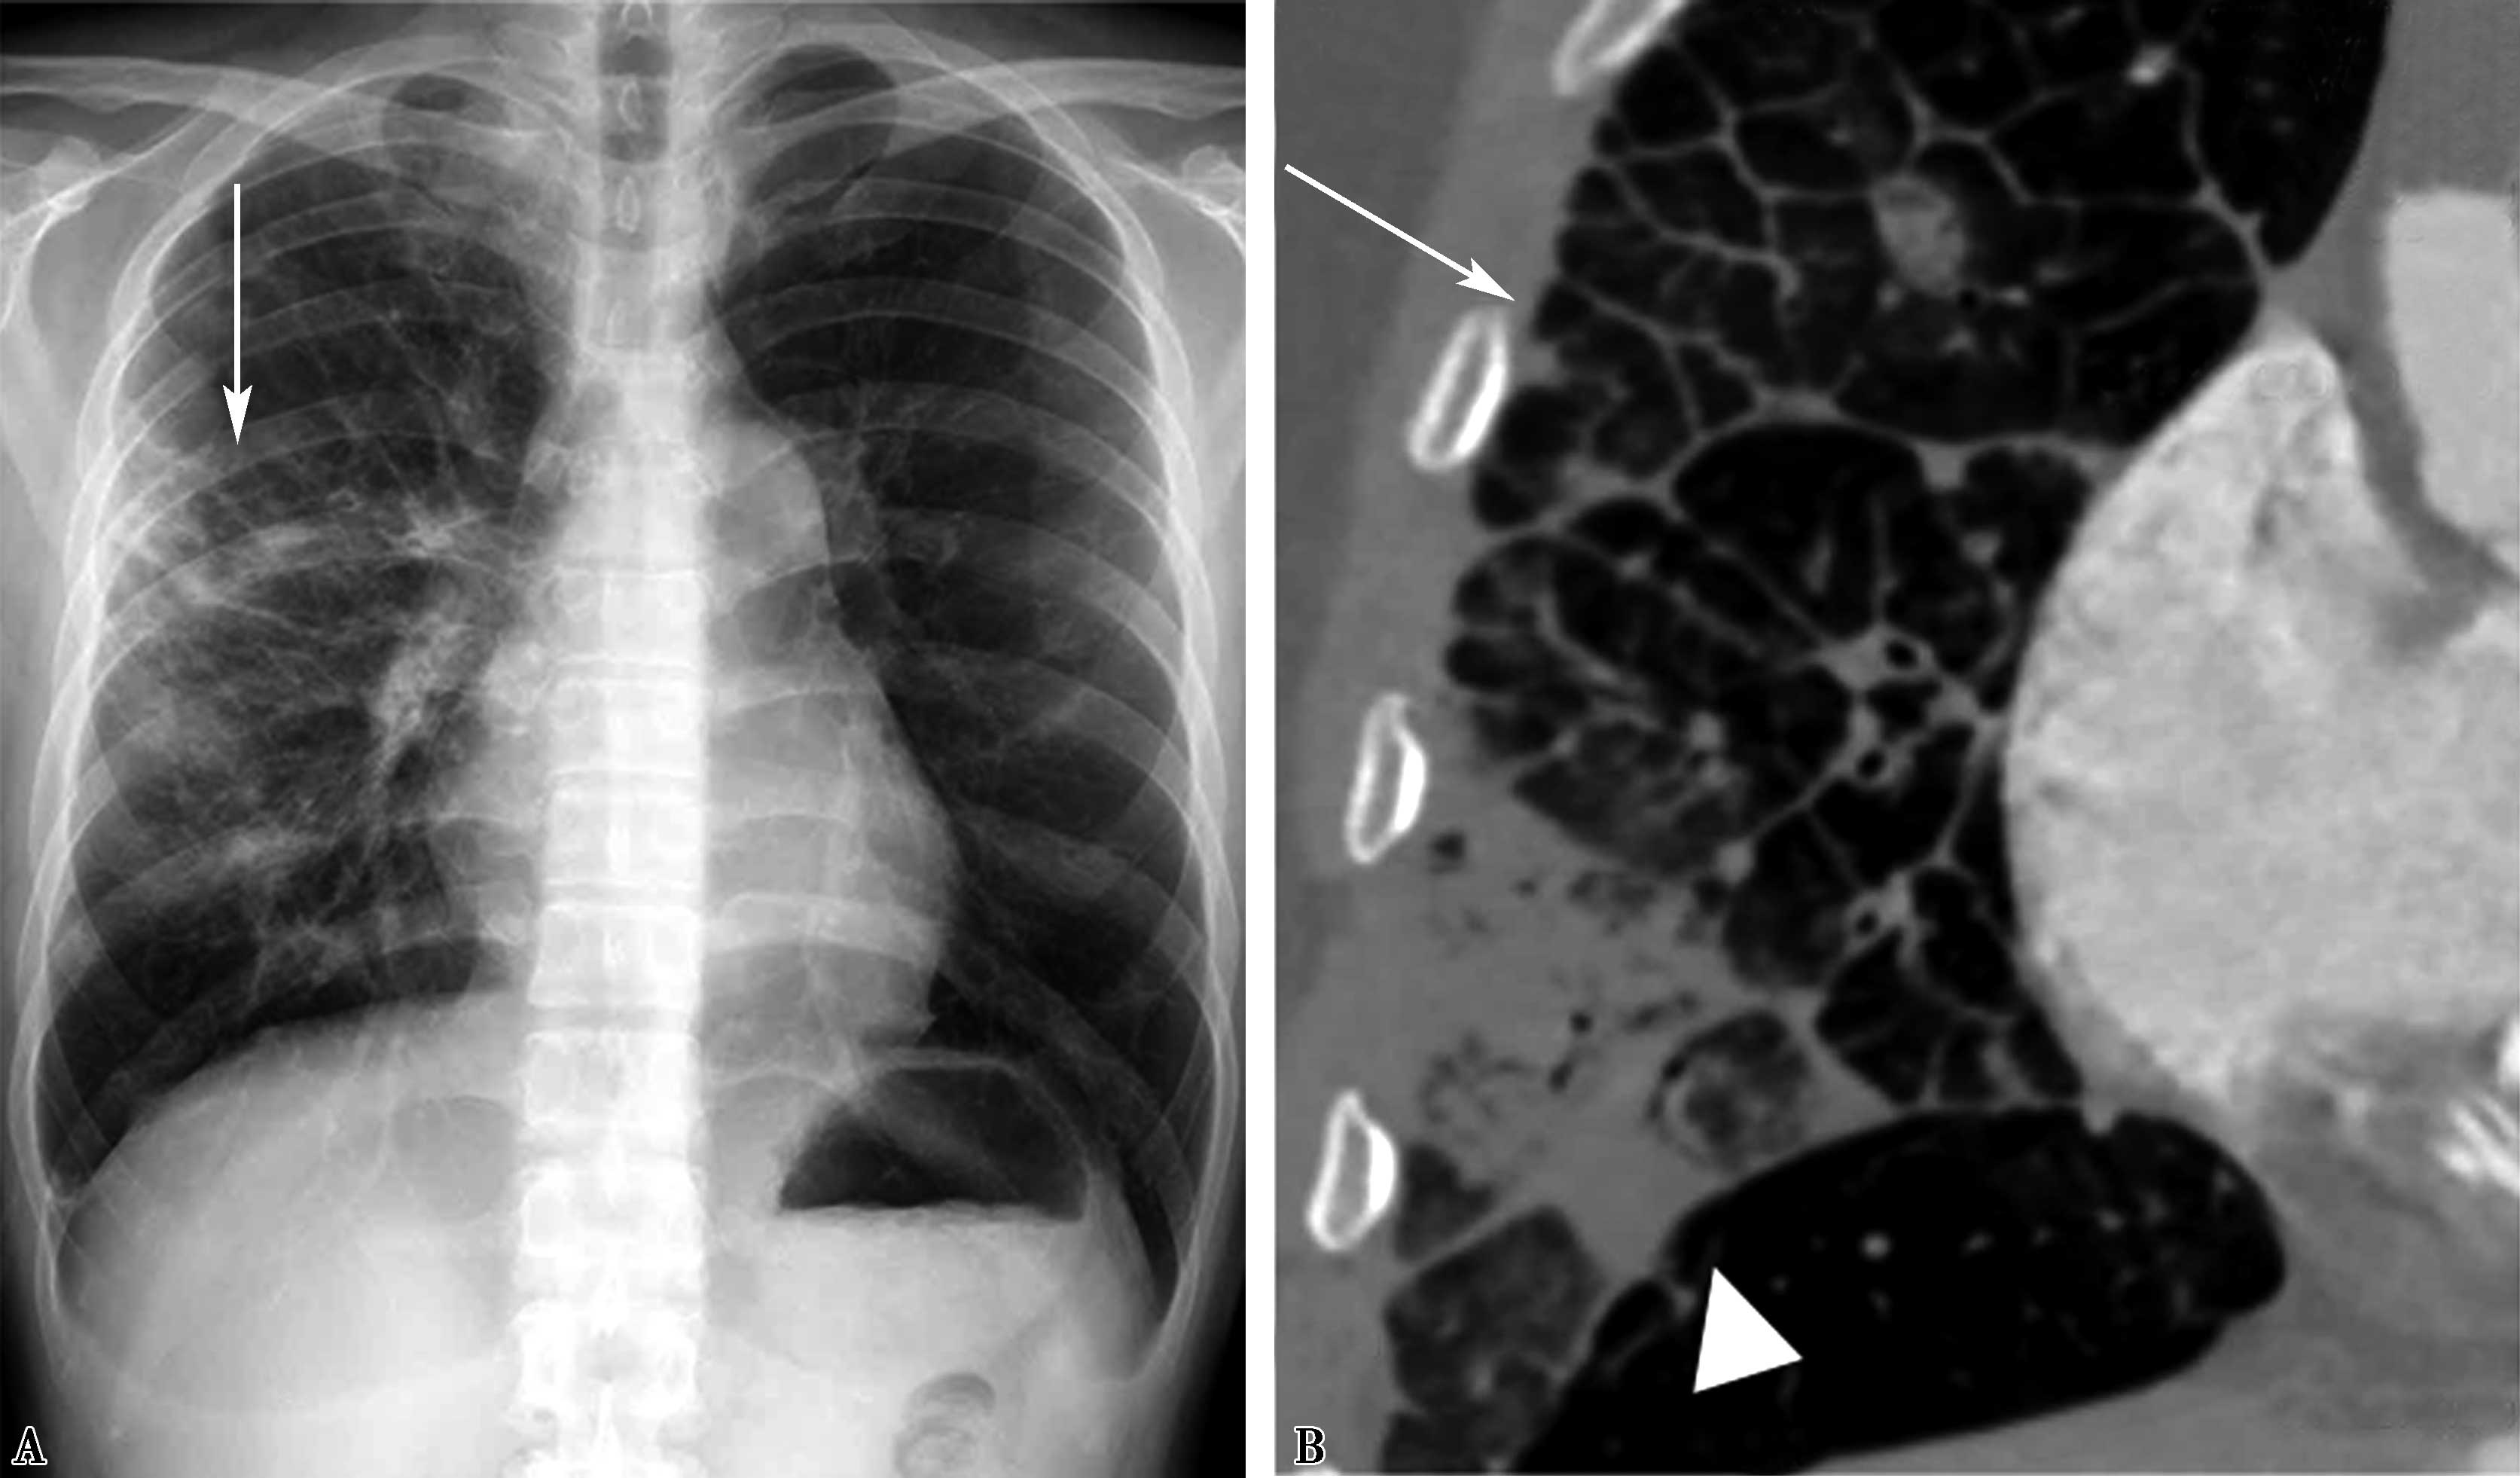

图7-2-7 右肺上叶及中叶肺水肿(间质性及肺泡性肺水肿)

造影证实为右上肺静脉闭塞;A.胸部正位;B.HRCT冠状位重建,可见典型小叶间隔增厚(↑),肺泡性水肿(▲)